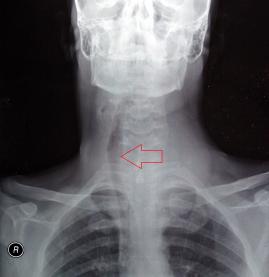

- Bu belirtiler sizde varsa tiroid hastalığınız olabilir !!